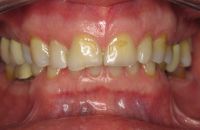

Na de behandeling met composiet

Door het composiet is er weer een dikke, stevige laag ontstaan aan de binnenzijde die niet snel zal afbreken. De tanden zijn hierdoor ook weer verlengd.